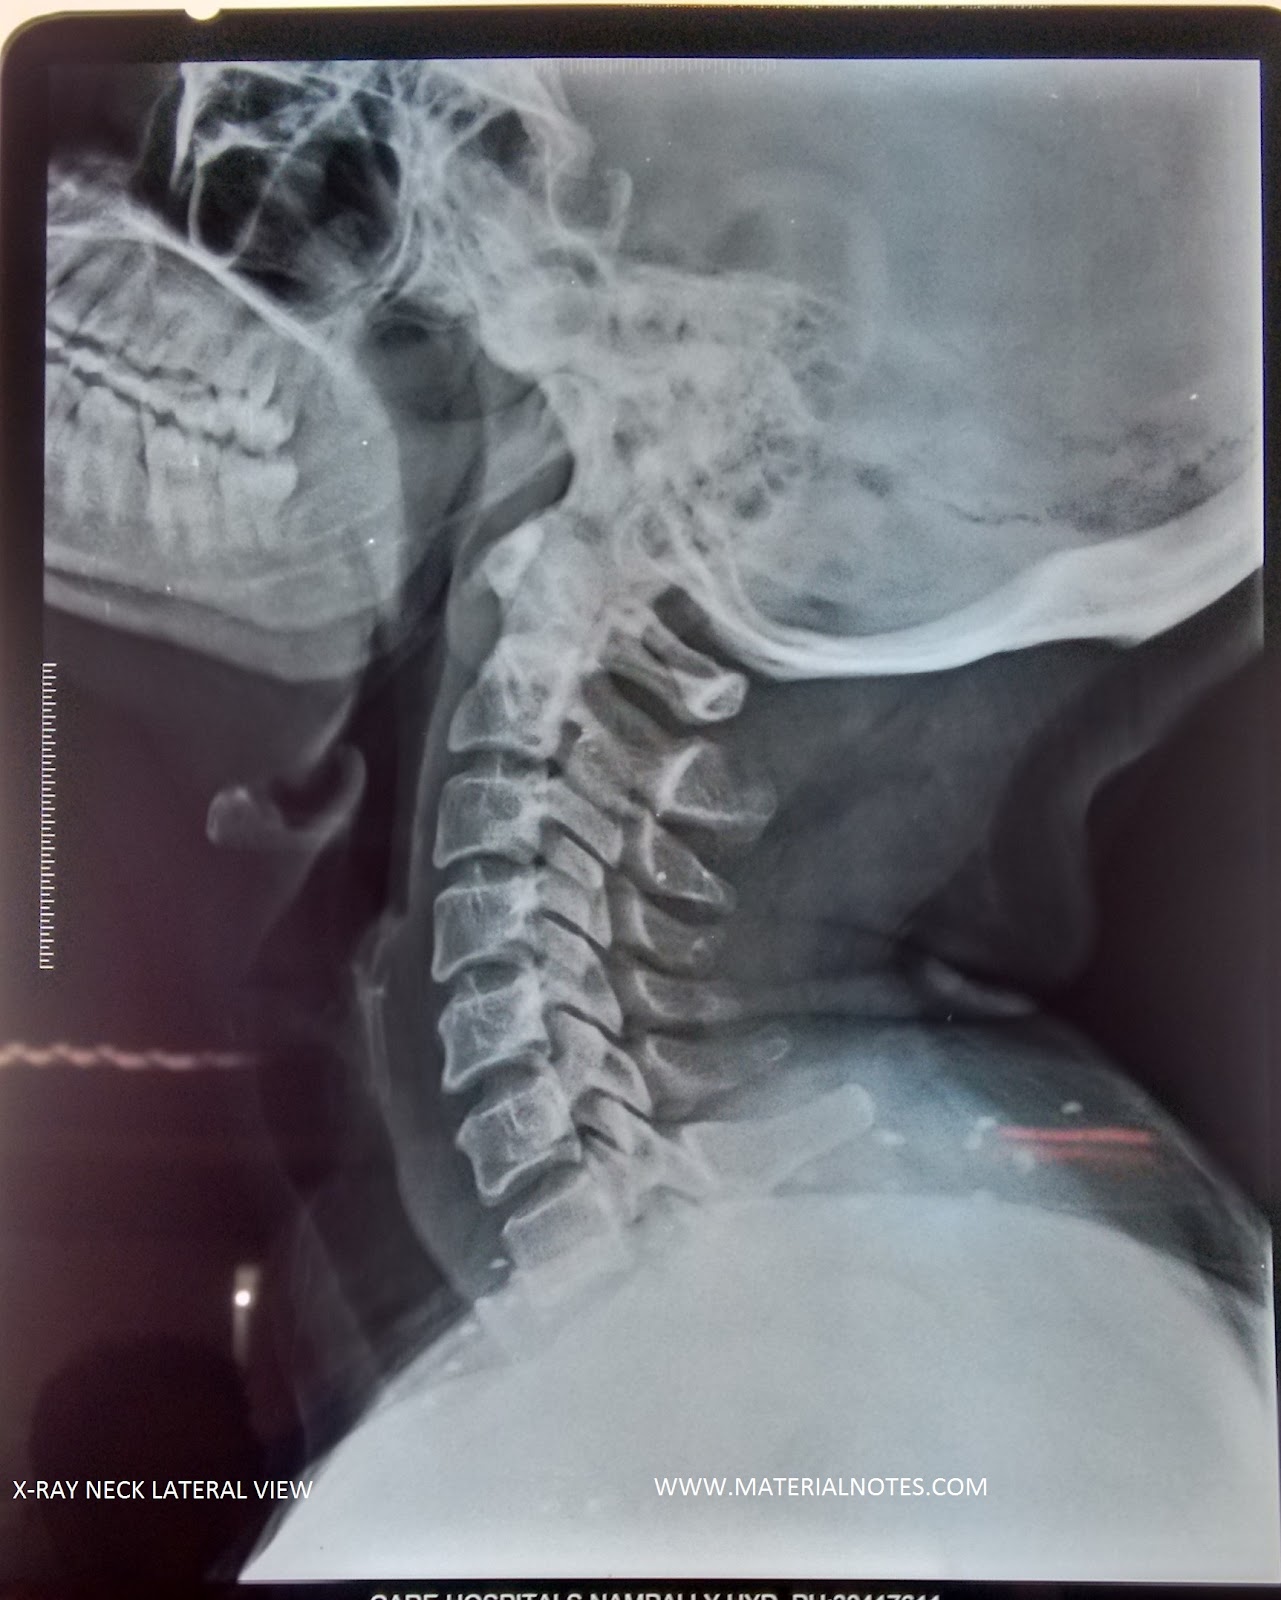

Рентген шеи белое пятно - фото презентация